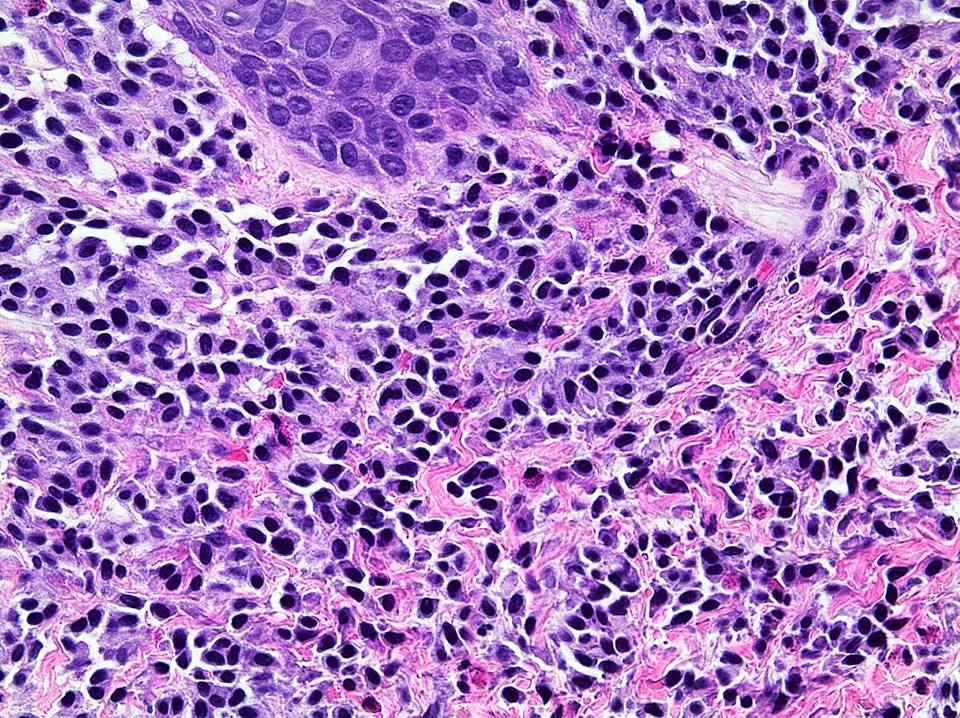

Microscopic (histologic) description

- Within the macules and plaque, mast cells are predominantly in papillary dermis

- Mast cells are round or spindle shaped with abundant eosinophilic cytoplasm, distinct cytoplasmic boundaries, large pale nuclei

- Eosinophils are often present

Microscopic (histologic) images